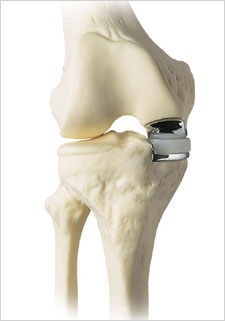

Figure: Example of a fixed bearing unicondylar knee replacement

(the images on top represent a preoperative joint; the images on the bottom represent a postoperative joint)